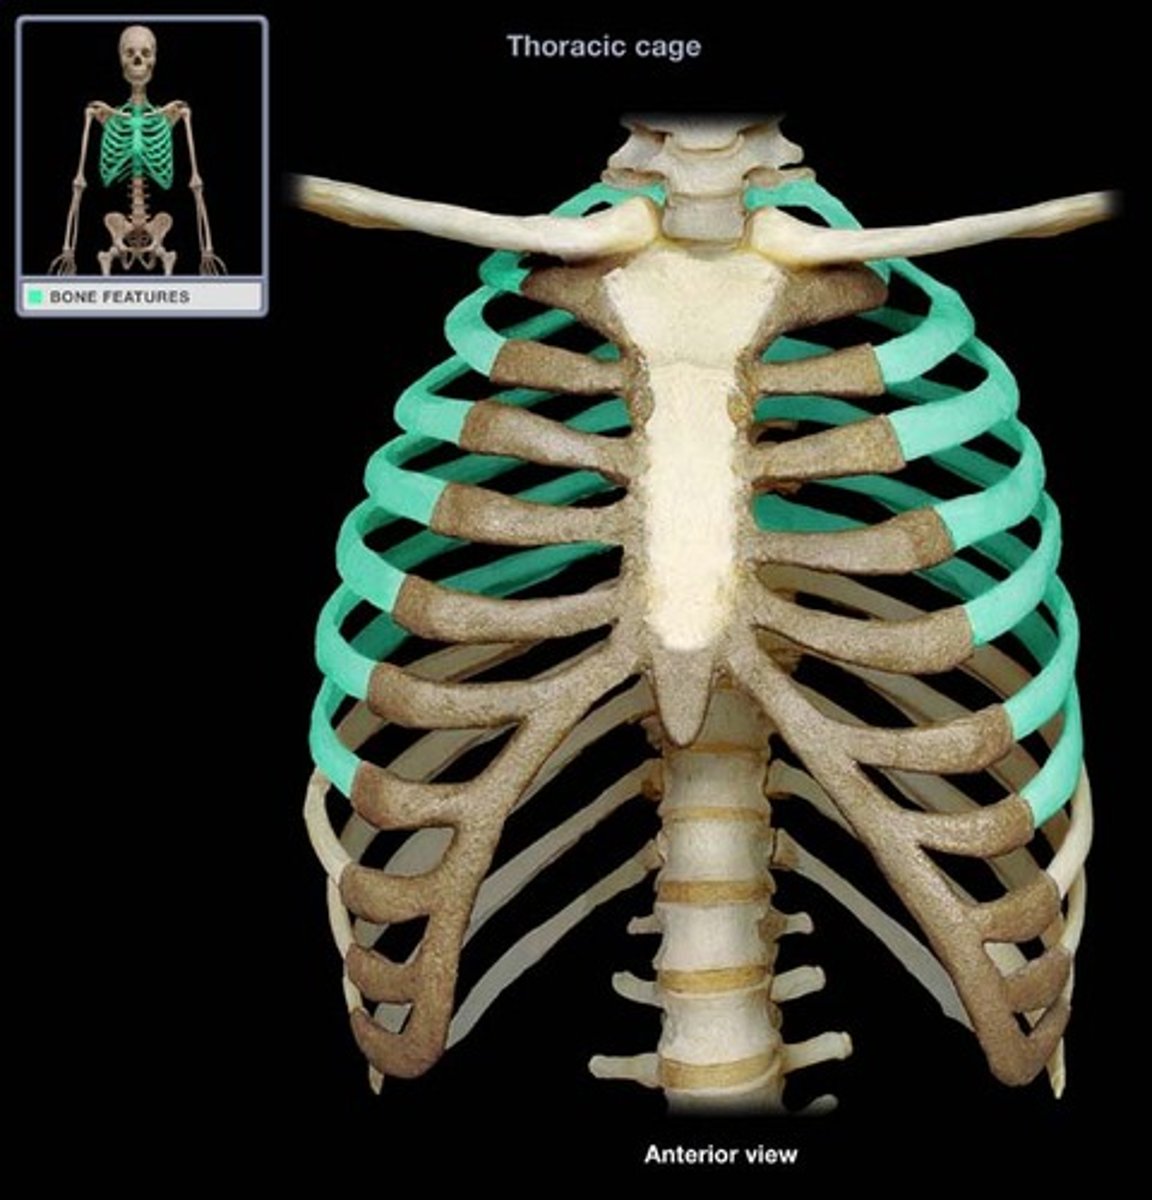

ribs

What is this bone?

true ribs

1-7

false ribs

8-12

floating ribs

11-12

costal cartilages

What is this structure?